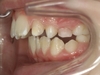

Inversion de l'occlusion des dents antérieures

L'inversion de l'occlusion des dents antérieures, également connue sous le nom d'occlusion croisée antérieure, se produit lorsque les dents inférieures se placent devant les dents supérieures. Cette malocclusion entraîne des problèmes de mastication, et peut induire des usures de l’émail et des problèmes de gencive sur les dents en inversé. Elle peut par ailleurs entraîner une glissement vers l’avant ou le côté de la mâchoire inférieure et en modifier la croissance.

Pourquoi traiter ?

Un traitement précoce permet de rétablir des contacts incisifs et une mastication efficaces, de protéger les dents et leur gencive, et de recentrer la mâchoire du bas si elle est contrainte par la malocclusion.